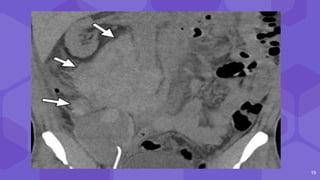

Abscesses

● Not frequent

● Early post renal

● Perirenal collection + febrile

● Plain CT - fluid collections

containing dense fluid

content

● CECT or gadolinium

enhanced MRI - postcontrast

enhancement of capsule

Perinephric

collection